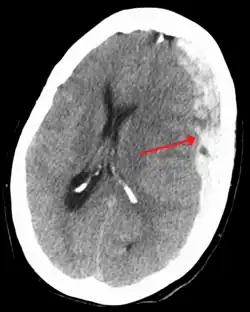

Subduralt hæmatom vist med pile med betydelig midtlinjeforskydning. | |

På en CT-skanning kan et SDH ses som en linseformet bramme med den konkave side mod hjernen. I den akutte fase ses det friske blod som klart hvidt på billederne, men senere vil den gå over i lysegrå i takt med at blodet reabsorberes. Til forskel for epidurale blødninger er SDHer ikke afgrænset af kraniets suturer og vil derfor brede sig over en større del af hjernens overflade. På hjernens overflade, umiddelbart under blødningen, kan der være hypodensitet (mørkfarvning) af hjernevævet, som tegn på iskæmi og medfølgende væskeansamling.